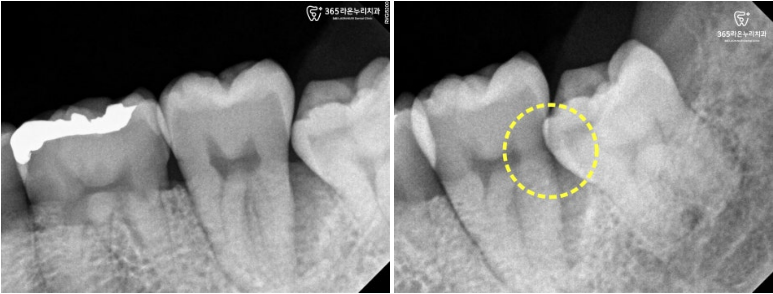

파노라마 사진으로 확인해보면,

턱 안쪽 깊숙이 완전히 매복된 사랑니가

통증의 원인인 경우가 자주 보입니다.

▮ 완전 매복 사랑니란?

잇몸 위로 전혀 보이지 않고

턱뼈 속에 완전히 묻혀 있는 상태를 말합니다.

수청동 치과 에서는 겉에서 봤을 때는

치아가 없는 것처럼 보여도,

이러한 치아는 뼈 속 깊은 곳에서

조용히 문제를 일으킬 수 있다고 설명합니다.

예를 들어,

왼쪽 아래 사랑니가

뼈 속에 완전히 묻혀 있는 경우라도,

그 앞에 있는 어금니 뒤쪽 잇몸이

살짝 열려 있는 채로

발견되는 일이 있습니다.

이렇게 잇몸이 벌어지게 되면,

그 틈을 통해 음식물 찌꺼기나 세균이

쉽게 들어가게 됩니다.

그런데 그 얇아진 잇몸 아래에는,

완전히 묻힌 매복치의 머리 부분이

바로 앞 치아 뿌리 근처에

위치해 있는 경우가 많습니다.

이 틈새로 들어간 세균이

염증을 일으키고,

시간이 지나면서

뼛속 깊은 조직까지 퍼지게 됩니다.

결국,

앞에 있는 어금니 뿌리 주변의 뼈가

녹아버리는 문제까지 생길 수 있습니다.